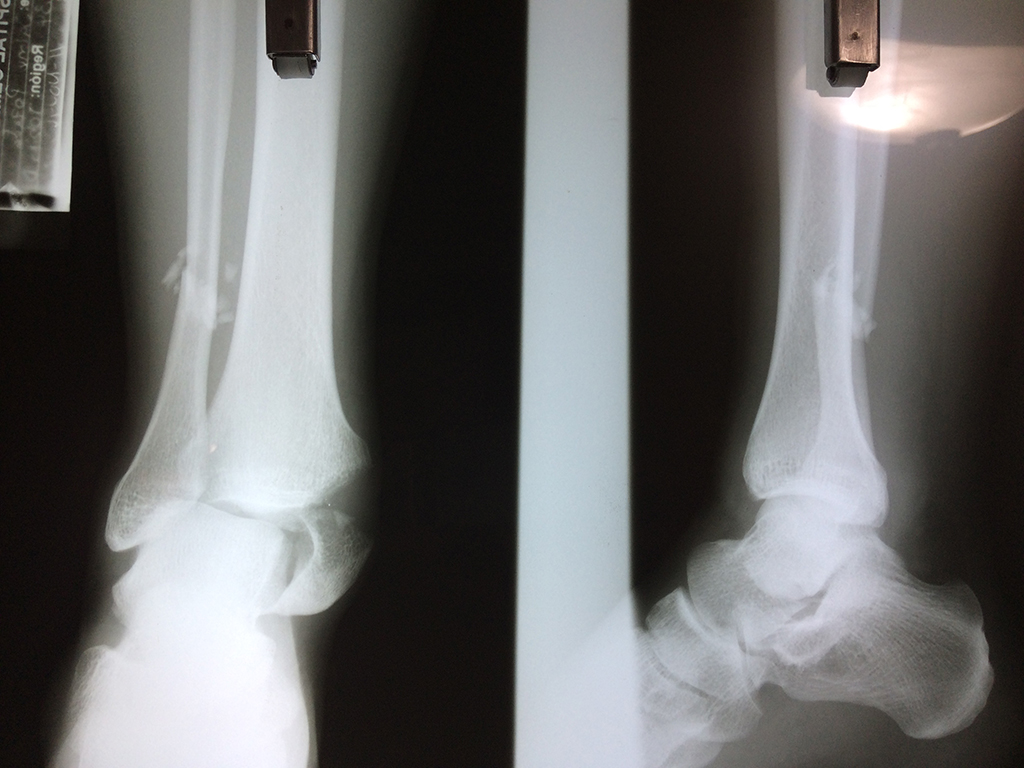

Una fractura de tobillo es la rotura de uno o más de los huesos del tobillo. Estas fracturas pueden ser:

- Parciales (el hueso está sólo parcialmente fisurado, no del todo).

- Completas (el hueso está perforado y está en 2 partes).

- Producirse en uno o ambos lados del tobillo.

Algunas fracturas de tobillo pueden requerir cirugía si:

- Los extremos de los huesos están desalineados entre sí (desplazados).

- La fractura se extiende hasta la articulación del tobillo (fractura intra-articular).